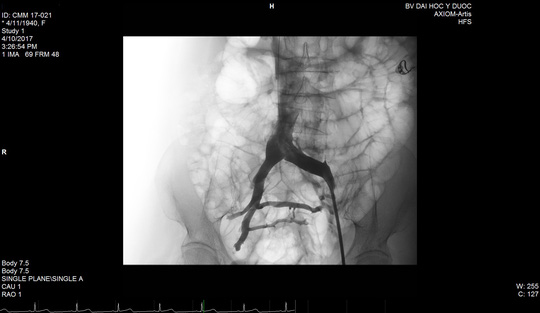

Lần đầu tiên đặt stent trị được suy tĩnh mạch

Sau 2 năm nghiên cứu và ứng dụng điều trị, Bệnh viện Đại học Y Dược TP HCM đã thành công với kỹ thuật mới trị bệnh suy tĩnh mạch chi dưới bằng cách đặt stent